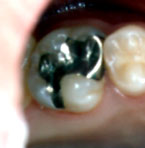

左上の第一大臼歯 |

これらの歯はみな

同じ患者さんの歯です。

レントゲンではどれも

むし歯の大きさは

同じくらいでした。

(他の歯科で治療する

前に撮ったレントゲン) |